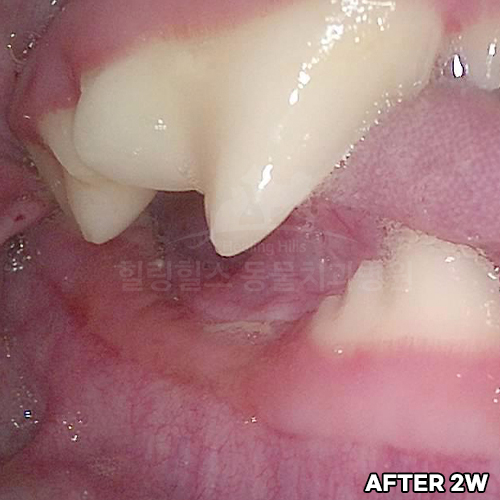

턱뼈 부러뜨리는 강아지치근단농양! 2.3kg 초소형견 발치하지 않고 신경치료하여 자기치아 살리는 힐링힐스